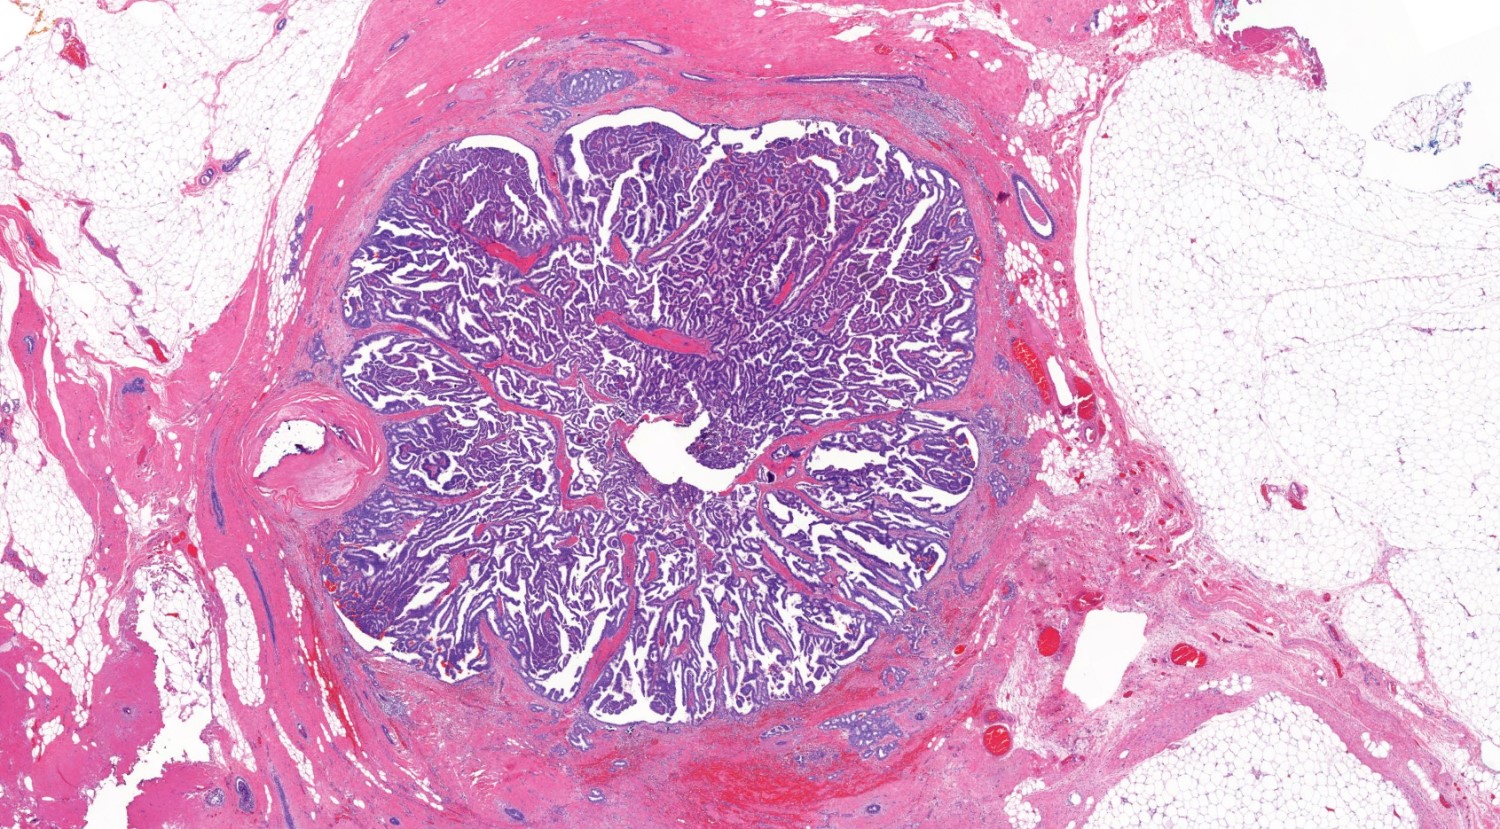

Microscopic (histologic) description

- Papillary tumor with pushing borders, may be within a cystically dilated duct, surrounded by a thick fibrous capsule (Histopathology 2008;52:20, Mod Pathol 2021;34:1044, Virchows Arch 2022;480:5)

- Delicate papillary fronds with fibrovascular cores lined by cuboidal to columnar epithelial cells with low to intermediate grade atypia

- Cribriform and solid architecture may be present

- Low mitotic activity (average 3 mitoses per 10 high power fields [HPFs]) (Am J Surg Pathol 2011;35:1)

- Most show complete lack of myoepithelial cells along the papillae and around the periphery of the tumor (Am J Surg Pathol 2006;30:1002, Am J Surg Pathol 2011;35:1)

- Basement membrane markers (collagen IV, laminin) may be expressed around the periphery (Pathobiology 2021;88:359, Am J Clin Pathol 2009;131:228)

- Invasive carcinoma is defined as the presence of neoplastic cells infiltrating beyond fibrous capsule (Mod Pathol 2021;34:1044)

Microscopic (histologic) images

Contributed by Kristen E. Muller, D.O. , Mariel Molina Nunez, M.D. and Julie Jorns, M.D. (Case #518)